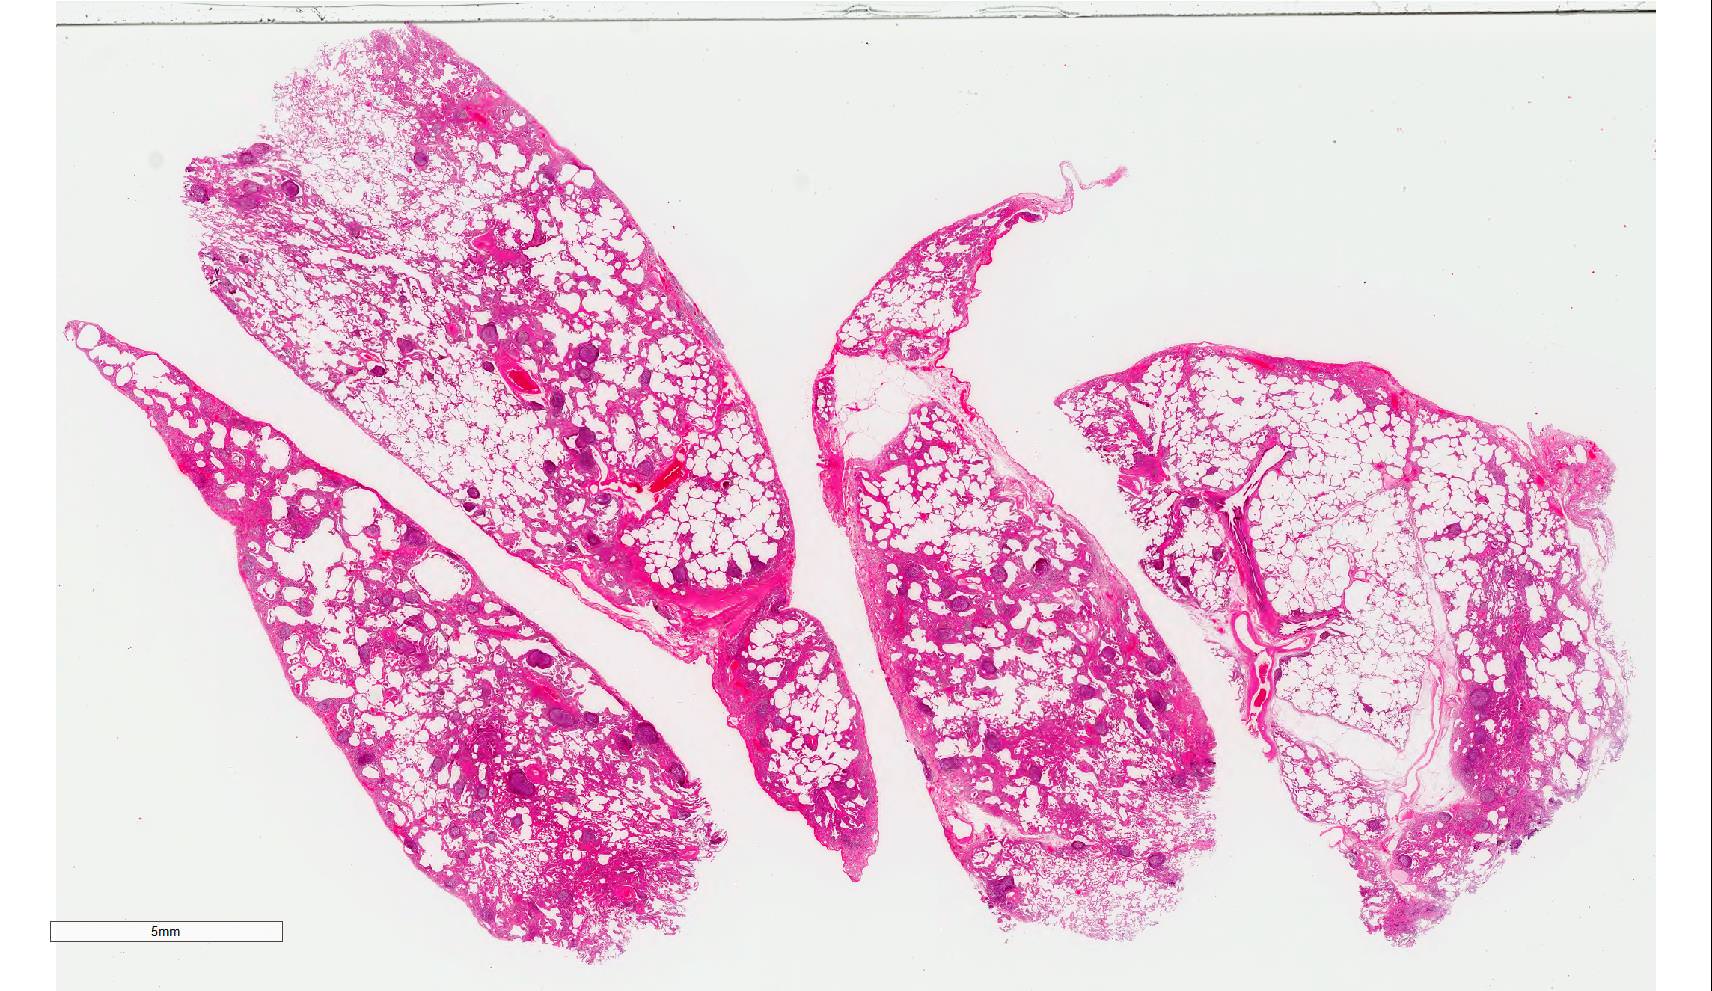

Gross description

- Diffuse involvement with mild to moderate increase in lung weight

- Fibrotic changes in lower lobes

- Homogeneous and diffuse compared to UIP

- Shrunken lung

- Traction bronchiectasis can be seen

- Honeycomb change can be seen but limited

Microscopic (histologic) description

- Diffuse and uniform inflammation ("temporal homogeneity") on low power of alveolar wall, bronchovascular bundles and pleura

Microscopic (histologic) images

Contributed by Akira Yoshikawa, M.D.

Contributed by Akira Yoshikawa, M.D.